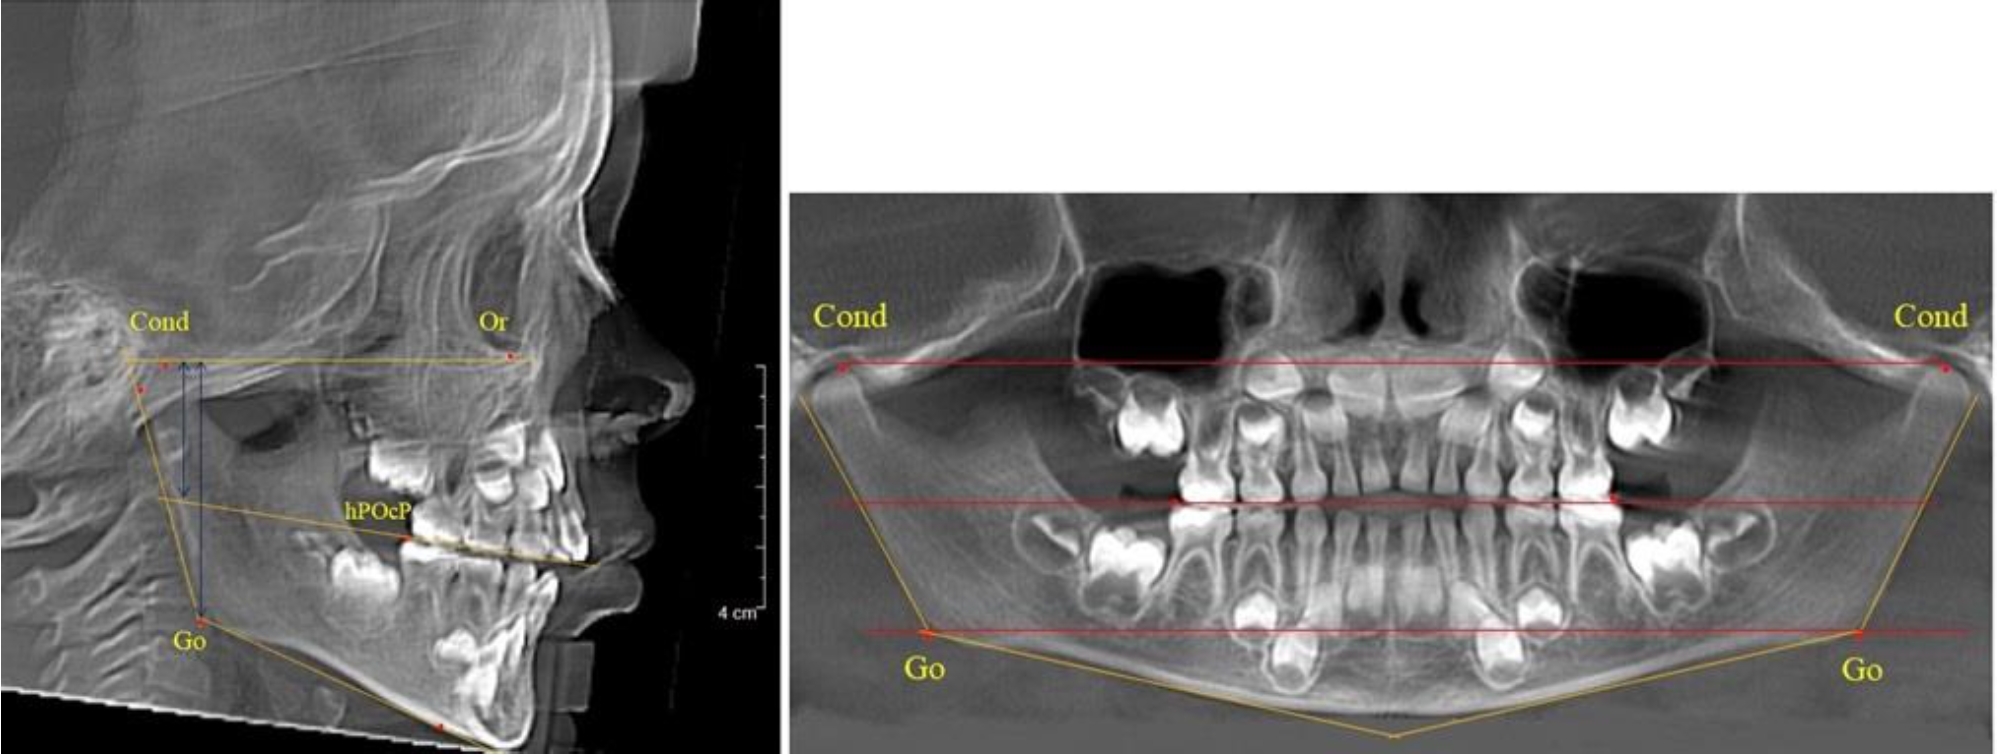

На всех парах рентгенограмм угол нижней челюсти, измеренный на телерентгенограмме, так же, как и в 1-й группе, соответствовал углу, полученному при построении угла на ортопантомограмме. Окклюзионная линия делила ветвь на два отдела (рис. 2).

Рис. 2. ТРГ и ОПТГ пациента после прорезывания первых постоянных моляров

Как на ортопантомограмме, так и на телерентгенограмме высота ветви у детей 2-й группы составляла (46,54 ± 2,87) мм, что было несколько больше, чем у детей 1-й группы (р ˂ 0,05). При этом высота верхней окклюзионно-суставной части была (25,42 ± 1,59) мм, а нижней – (21,12 ± 1,77) мм.

Таким образом, верхняя часть была несколько больше нижней, что и определяло рост обеих частей ветви.

Относительные показатели соразмерности частей ветви нижней челюсти показали, что отношение высоты верхней части ветви к нижней в среднем составляло 1,21 ± 0,12. Отношение общей высоты ветви к верхней ее части составляло 1,83 ± 0,13, а отношение общей высоты ветви к нижней ее части было 2,20 ± 0,16, и достоверных различий по относительному показателю отношения всей высоты к верхней и нижней челюсти нами не отмечено (р ˃ 0,05).